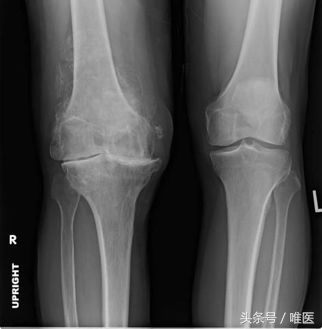

早期的膝关节骨关节炎,可以通过药物治疗,物理康复治疗等方法缓解,中晚期的膝关节骨性关节炎,保守治疗通常难以得到满意的效果,尤其是晚期的骨关节炎,从X线片上就能发现明显的病变。严重程度不同的骨关节炎,治疗的方法是不一样的,并不是所有的骨关节炎都需要手术治疗,同样,也并非所有的骨关节炎都可以通过药物控制。比如下面同一个病人的两个膝关节,病变处在不同的阶段,接受的治疗也不一样。

x线下两个膝关节的病变轻重明显不同